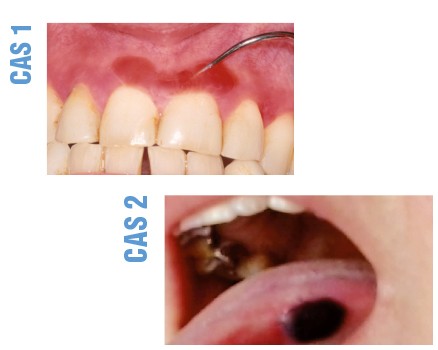

CAS 1

Patiente, âgée de 69 ans, traitée pour une gingivite, mais qui, malgré les soins, présentait une aggravation de son affection.

Depuis 18 mois, présence d’une inflammation de la fibro-muqueuse gingivale, principalement vestibulaire, qui évoluait de façon cyclique.

Il existait un érythème diffus mais irrégulier, intéressant la fibro-muqueuse gingivale vestibulaire, surtout supérieure. L’érythème, peu marqué, n’était pas limité au bord libre de la gencive et pouvait toucher la fibro-muqueuse sur toute sa hauteur. Dans la région médiane supérieure, on observait une large bulle avec un contenu hémorragique.

La biopsie et l’examen en immunofluorescence directe ont confirmé le diagnostic de pemphigoïde cicatricielle des muqueuses.

Synthèse. La pemphigoïde cicatricielle des muqueuses est une maladie bulleuse auto-immune qui touche principalement la fibro-muqueuse gingivale, surtout chez des femmes âgées. Elle est souvent initialement considérée comme une banale gingivite. En phase d’activité, on peut observer un dépôt blanchâtre au collet des dents correspondant à un exsudat fibrineux. Comme ce dépôt se forme rapidement et qu’il ressemble à de la plaque, les patients sont régulièrement accusés d’être responsables de leur gingivite en raison d’une hygiène bucco-dentaire insuffisante. L’examen microscopique montre un décollement sous-épithélial avec un dépôt linéaire d’IgG et de C3 sur la membrane basale. Il existe une dizaine d’antigènes-cibles, mais le plus fréquent est le BPAg2 de 180 kD. Il faut systématiquement…